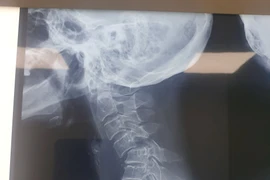

(khoahocdoisong.vn) - Đa phần bệnh nhân bị gãy trật cột sống cổ sẽ bị liệt hoặc tử vong. May mắn một bệnh nhân nữ 70 tuổi đã được phẫu thuật cứu sống không để lại di chứng sau 5 ngày bị gãy trật đốt sống cổ C4-C5 độ III.

Gãy cột sống đe doạ trực tiếp đến tính mạng đồng thời để lại di chứng rất nặng như: liệt tứ chi, mất cảm giác, khó hồi phục được kể cả khi đã phẫu thuật.